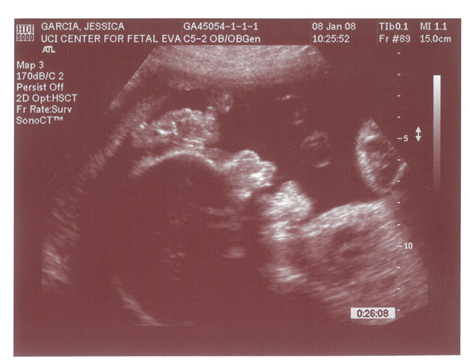

Yes we got a new dsmer coming into the world soon. We got our ultrasound today and its gonna be a boy. And shes a lot further along then we had originally thought. Shes due on April 15th which puts her at almost 6.5 months, (and really not showing it.) He weighs currently ~2lbs. He even opened his mouth while on camera which was really cool.

Here are the pics.

Pic 4: Long little legs!

Pic 5: Big Feet just like his mama.